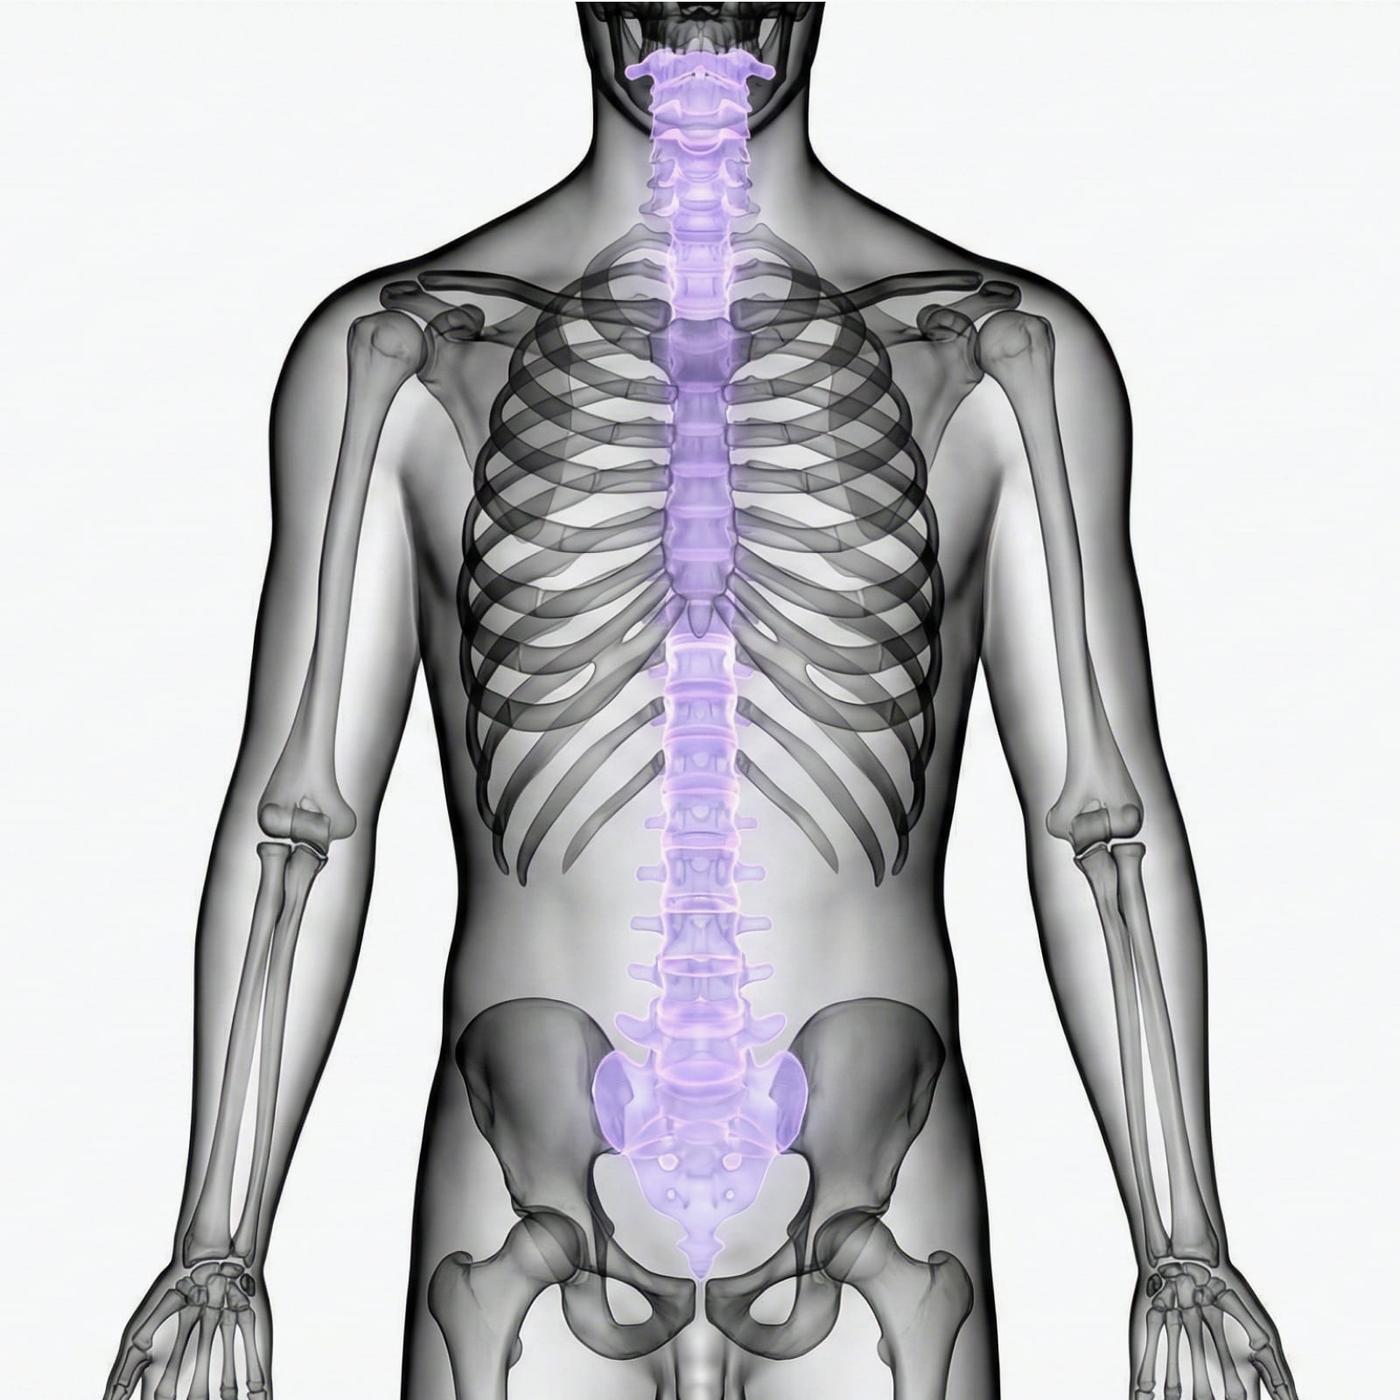

Magnetkameraundersökning (MR) av hela ryggraden – hals-, bröst- och ländrygg

MR Helrygg är en avancerad magnetkameraundersökning som omfattar hela ryggraden, från halsrygg (cervikal) och bröstrygg (thorakal) till ländrygg (lumbal). Undersökningen ger en detaljerad bild av samtliga delar av ryggraden och omgivande strukturer, vilket gör det möjligt att identifiera både akuta och kroniska förändringar. Eftersom undersökningen täcker alla ryggsegment rekommenderas den framför allt för dig som har mer omfattande eller diffusa besvär som inte kan lokaliseras till en specifik del av ryggen.

Vad ingår i en MR Helrygg?

Undersöknigen omfattar samtliga tre huvudsegment i ryggraden.

MR Halsrygg (cervikal ryggrad)

Undersökning av nackens kotor, diskar och ryggmärg. Här kan bland annat diskbråck, nervpåverkan och förträngningar i spinalkanalen identifieras.

MR Bröstrygg (thorakal ryggrad)

Bröstryggen utgör den mellersta delen av ryggraden och skyddar ryggmärgen genom bröstkorgen. MR kan påvisa exempelvis inflammation, tumörer eller strukturella förändringar.

MR Ländrygg (lumbal ryggrad)

Ländryggen är ett vanligt område för smärta och nervpåverkan. MR används ofta för att upptäcka diskbråck, spinal stenos och degenerativa förändringar.